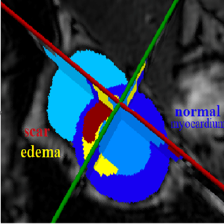

来自ISICDM 2019 临床数据分析挑战赛的基于磁共振成像的膀胱内外壁分割与肿瘤检测数据集。

【灰度值】:灰色128为膀胱内外壁,白色255为肿瘤。

【分割任务】:同时分割出膀胱内外壁和肿瘤部分

【分析】:我们需要分割出膀胱内外壁和肿瘤,再加上黑色背景,相当于是一个三分类问题。